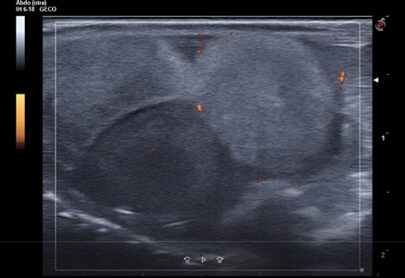

Seguiment: Porten el saure als 15 dies de la primera visita, segueix inflat i cada vegada menja menys, no han vist en el terrari la posada. Es realitza ecografia de control i s’observen 4 fol·licles preovulatoris, 2 d’ells hiperecogènics i 2 amb aspecte normal, i la típica imatge ecogènica amb centre circular hipoecogènic (figura 4).

Fig 3. Fol·licles preovulatoris. S’aprecia el cercle anecogènic típic al seu interior (ecografia del dia de la primera visita)